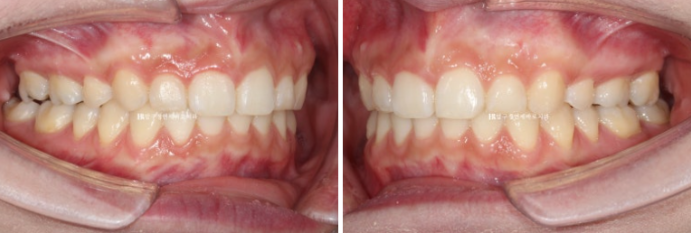

환자분이 고치고 싶은 것은 두가지가 있었습니다.

돌출입과 웃을 때 잇몸이 많이 보이는 거미스마일 이었습니다.

과개교합이 심해서 윗니에 덮여 아래 앞니가 보이지 않습니다.

좌 - 치료 전 우 - 치료 후

22.09~24.12